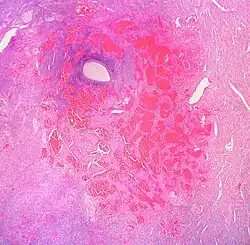

Анатомическое и гистологическое строение гемангиом

.jpg)